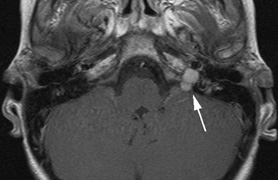

syndrome in 1926. The term von Hippel-Lindau syndrome (VHL) was

first used in 1936.166 The first major clinical criteria for the syndrome were proposed in 1964.167 The main manifestations of von Hippel-Linau syndrome are: histologically similar hemangiomas of the retina and CNS, renal cysts, renal cell carcinomas, pancreatic cysts, pheochromocytomas, and endolymphatic sac tumors.13 EPIDEMIOLOGY The prevalence of VHL syndrome is about 1 in 35,000 to 40,000.168 It is autosomal dominant with greater than 95% penetrance by age 60 years.169 Its expression, even within the same family, may be quite variable, especially for renal disease and pheochromocytoma.170,171 SYSTEMIC FEATURES Cutaneous Findings Cutaneous findings are not part of the diagnostic criteria for VHL syndrome. Neurologic Findings CNS hemangiomas are the most common tumor of VHL, affecting 60% to 80%, with a predilection for the cerebellum and spinal chord. An enlarging cystic component is a frequent finding in symptomatic tumors. Patients typically present in their early 30s; headaches or neck pain in affected individuals should not be ignored.172,173 On microscopy, CNS hemangiomas resemble retinal capillary hemangiomas. Their malignant potential is low.174 The treatment is surgical (Fig. 17, A and B).13 Endolymphatic sac cystadenomas are a sensitive marker of VHL. Patients may present with hearing loss, tinnitus, disequilibrium or facial nerve palsy.175,176 Visceral Findings KIDNEY. Renal cysts are often asymptomatic and do not require treatment. However, complex cysts may carry a risk for malignant transformation. Renal carcinoma affects about a third of patients. Patients typically present in their late 30s. These tumors may be completely asymptomatic, underscoring the necessity for ultrasound screening.13,177 ADRENALS. Pheochromocytomas are benign neural crest tumors of the adrenal medulla (chromaffin cell derived) and probably affect 10% to 20% of patients. Mean age at diagnosis is at about 30 years of age. Pheochromocytomas may be multiple and bilateral. They are catecholamine-secreting tumors that classically produce severe hypertension and anxiety attacks, but they may also be asymptomaic.178 The National Cancer Institute classification of VHL syndrome is in part based on the absence (type I) or presence (type II) of pheochromocytoma (Table 5).171